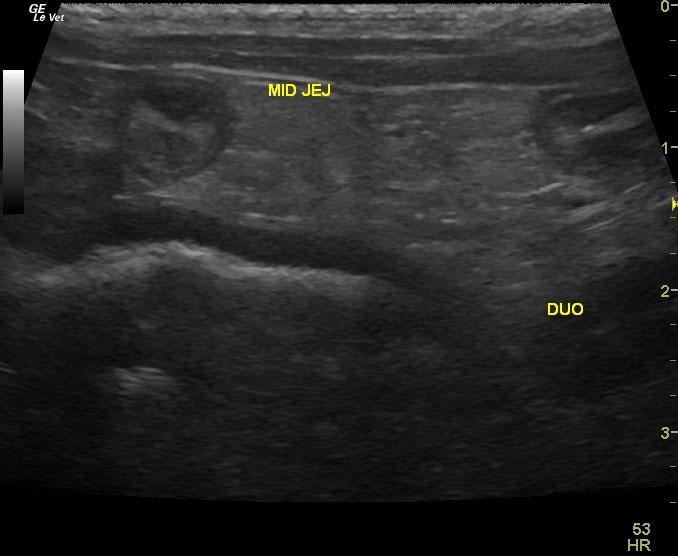

A 9 year old MN Maltese dog was presented for evaluation of progressive anorexia and soft feces. Physical examination and rectal palpation were both within normal limits. Fecal and urinalysis, CBC, serum biochemistry, cPl, and survey radiographs of the thorax and abdomen were all within normal limits.